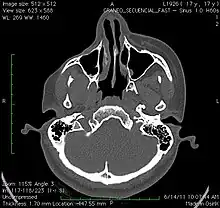

- A 3D, soft tissue reconstruction of a CT scan of a 17-year-old girl with Parry Romberg syndrome.

- CT scan3D bone reconstruction of a 17-year-old girl with Parry Romberg syndrome.